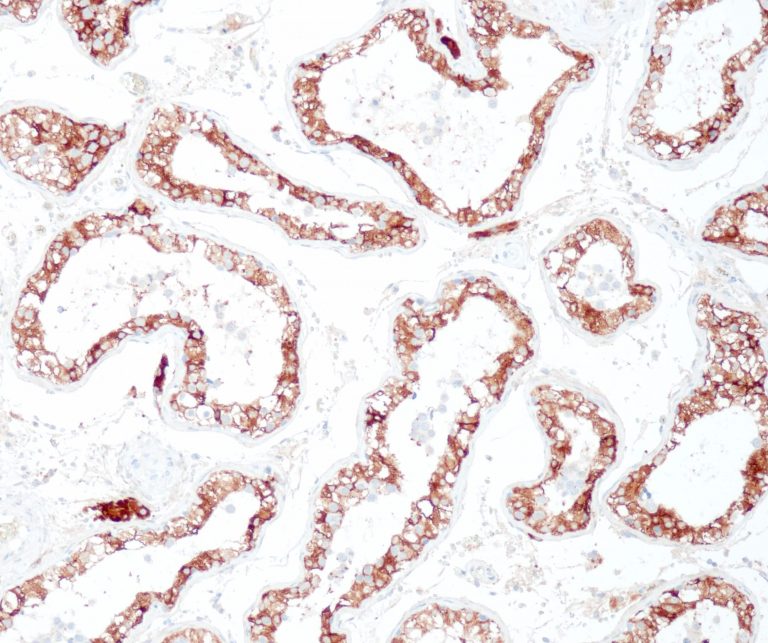

Breast Pathology